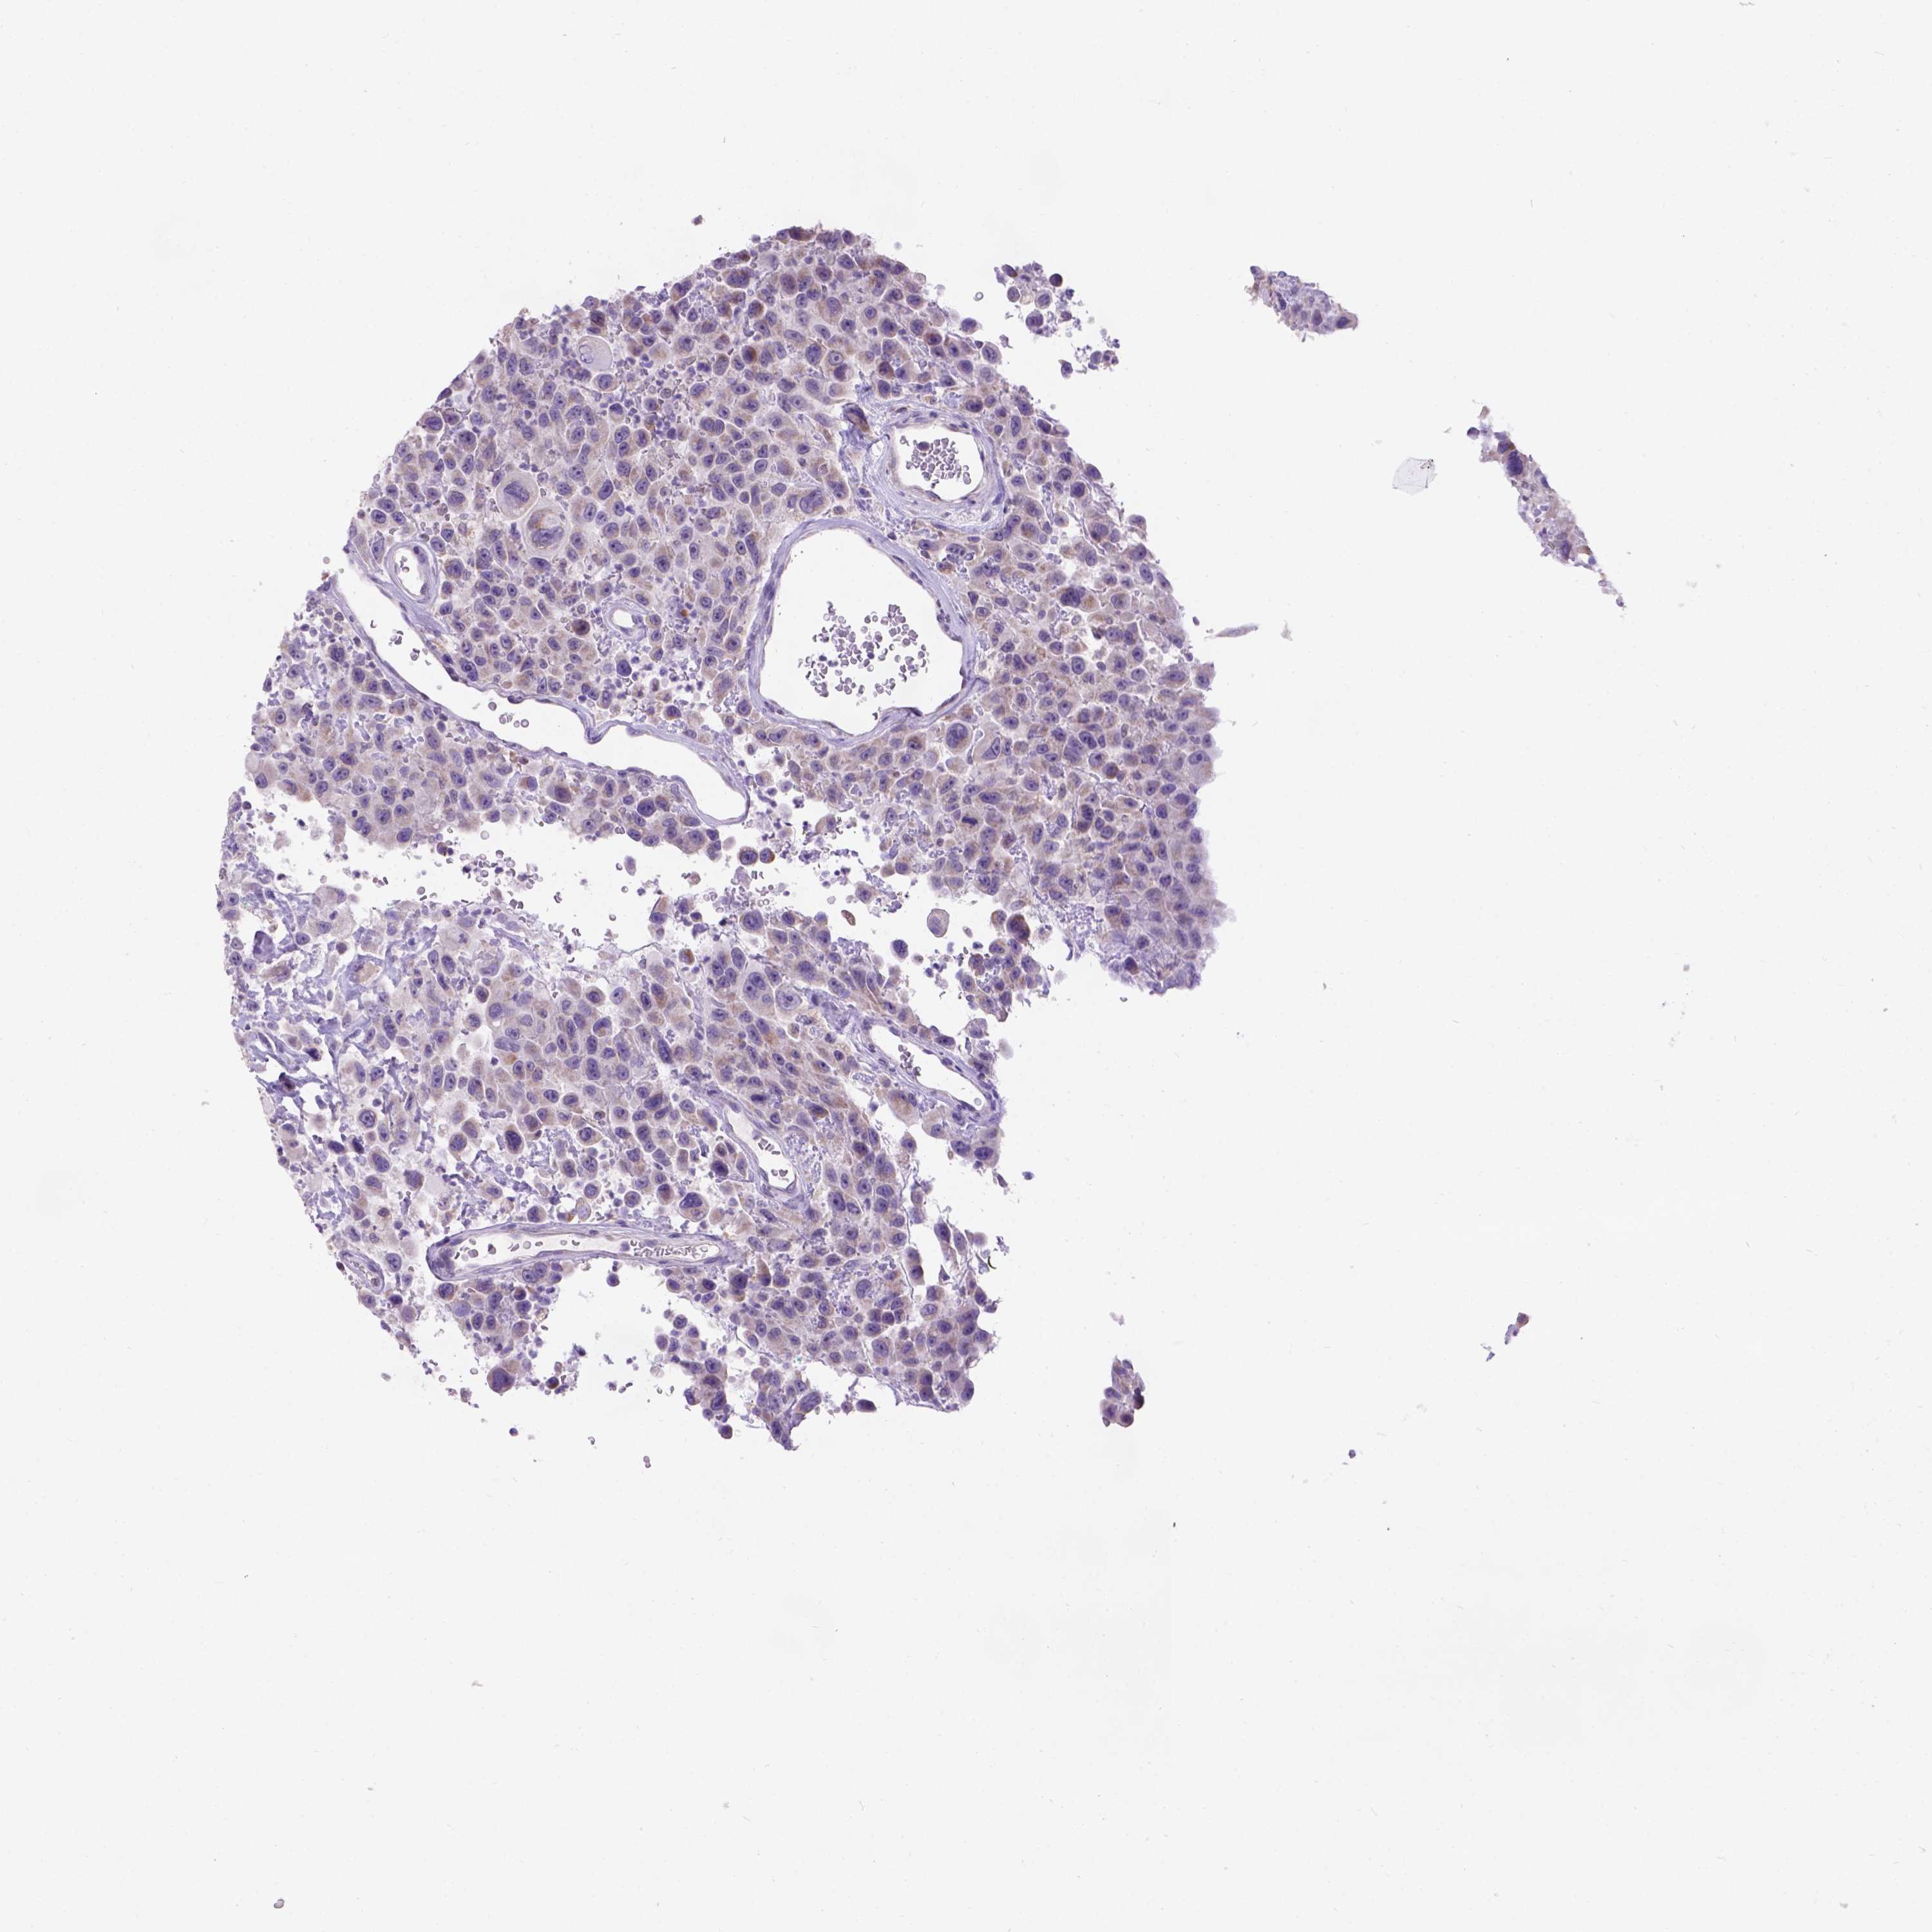

UROTHELIAL CANCER - Protein expressioni

A mouse-over function shows sample information and annotation data. Click on an image to view it in a full screen mode. Samples can be filtered based on level of antibody staining by selecting one or several of the following categories: high, medium, low and not detected. The assay and annotation is described here.

Antibody stainingi

Antibody staining in the annotated cell types in the current human tissue is reported as not detected, low, medium, or high, based on conventional immunohistochemistry profiling in selected tissues. This score is based on the combination of the staining intensity and fraction of stained cells.

Each image is clickable and will lead to virtual microscopy that enables deeper exploration of all samples and also displays staining intensity scores, fraction scores and subcellular localization as well as patient and tissue information for each sample.

Antibody HPA065409

Staining

High

Medium

Low

Not detected

Intensity

Strong

Moderate

Weak

Negative

Quantity

>75%

75%-25%

<25%

None

Location

Nuclear

Cytoplasmic/membranous

Cytoplasmic/membranous,nuclear

Urothelial carcinoma, High grade

Urothelial carcinoma, NOS

Urothelial carcinoma, Low grade